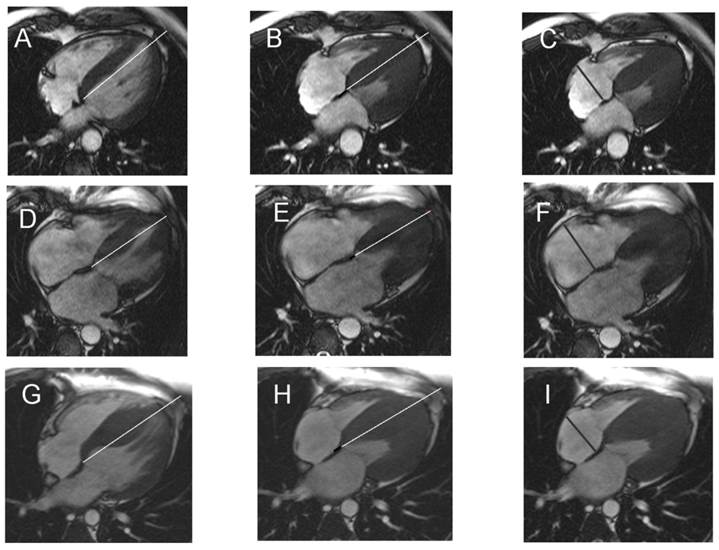

Representative Figure. In patients with HCM remaining in sinus rhythm (A-C), in those with atrial fibrillation at intial diagnosis (D-F) and those developing atrial fibrillation during follow-up (G-I), septal MAPSE (black line B,E, H) was calculated by subtracting the end-systolic (B, E, H) from the end-diastolic length (A, D, G) and the RAD (C, F, I) was determined.

Looking at the LGE extent % in HCM patients who remained in SR (11±12%) compared to those who presented with AF at initial diagnosis (16±16%) or during follow-up (17±18%) showed a trend towards more LGE (16±16%, p=0.2 and 17±18%, p=0.1, respectively). In relation to patients with HCM in SR, those who presented with AF at initial diagnosis (Table 3) were significantly older (p=0.01), revealed significantly elevated indexed LA volumes (p=0.004), significantly reduced septal MAPSE (p=0.01, Figure 1 D, E), significantly reduced TAPSE (p=0.03) and dilated RA (RAD, p=0.01, Figure 1 F).

Comparing patients with HCM in SR (Figure 1 A-C) with those who developed AF during follow-up (Figure 1 G-I), the latter presented with significantly reduced septal MAPSE (p=0.01), significantly diminished TAPSE (p=0.02) and significantly higher RAD (p=0.01).